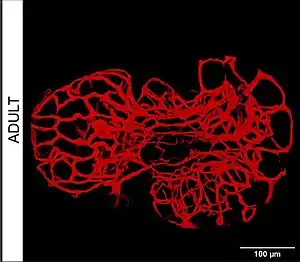

Microvasculatura

La microvasculatura o microvasos son aquellos vasos sanguíneos con un diámetro igual o menor a 100 micras y sus estructuras asociadas. La red microvascular se extiende dentro de los tejidos permitiendo que la sangre sea distribuida homogéneamente para realizar eficazmente su función. Este flujo sanguíneo se denomina microcirculación.

Las estructuras que conforman la microvasculatura son:

- las arteriolas,

- los capilares y

- las vénulas.